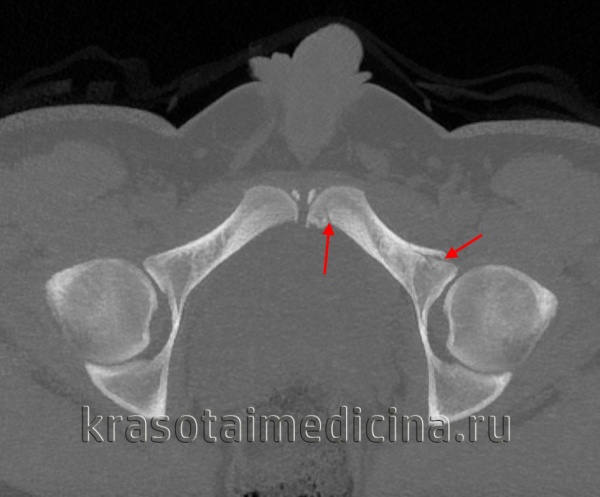

· компьютерная томография – является чувствительной и позволяет оценить целостность заднего отдела таза, а также можно определить размер и локализацию гематомы.

Компьютерная томография. При затруднении четкой интерпретации обзорной рентгенограммы из-за суперпозиции костей назначается компьютерная томография таза.